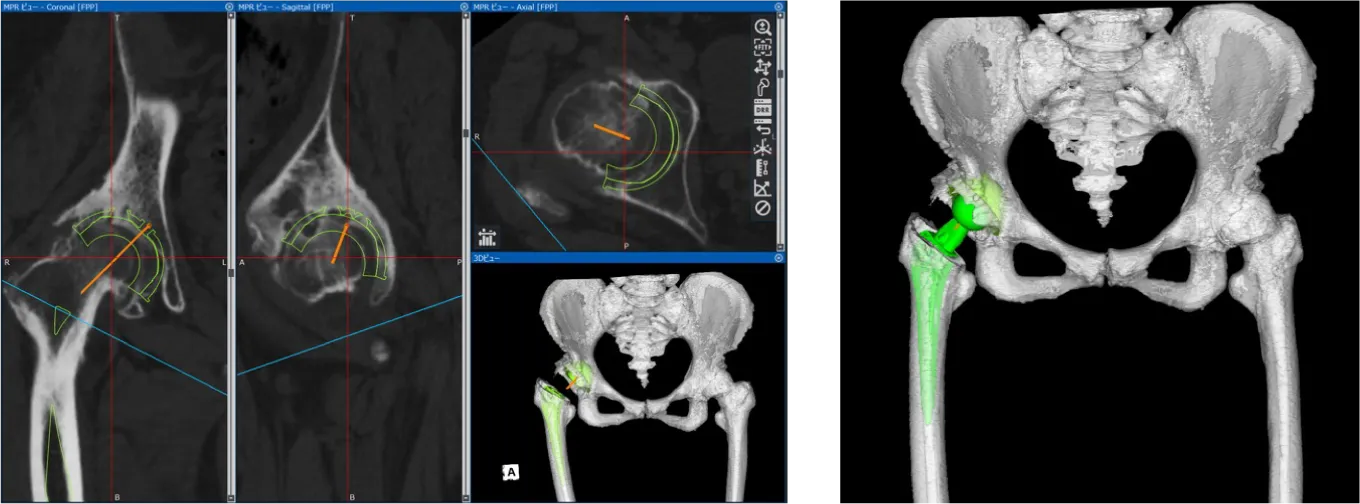

人工股関節置換術

主に変形性股関節症に対して行われる手術です。人工関節の中では、膝関節に次いで多く、日本で年間約7万件行われていると言われています。人工関節材料や手術方法が目覚しく発展し、耐用年数は大幅に伸びています。

現在は手術後20年経過しても、約80%の患者さんで入れ替えが不要と言われています。当院では膝関節同様、手術前に撮影したCTを元に、3次元的な術前計画を行い、個々の骨形態に対し適格な設置位置を確認しています。さらに術中簡易ナビゲーションを使用し、より正確な設置ができるよう心がけています。人工股関節手術は骨を扱う手術のため、術中に骨から出血を起こします。

当院では、手術中に出血した血液を回収し、専用の機器で不純物を取り除き、洗浄した後に輸血をする、術中回収式自己血輸血を導入しています。この方法により、いわゆる通常の輸血を行う頻度を減らすことができます。

3次元術前計画

• 術前レントゲン

• 術後レントゲン